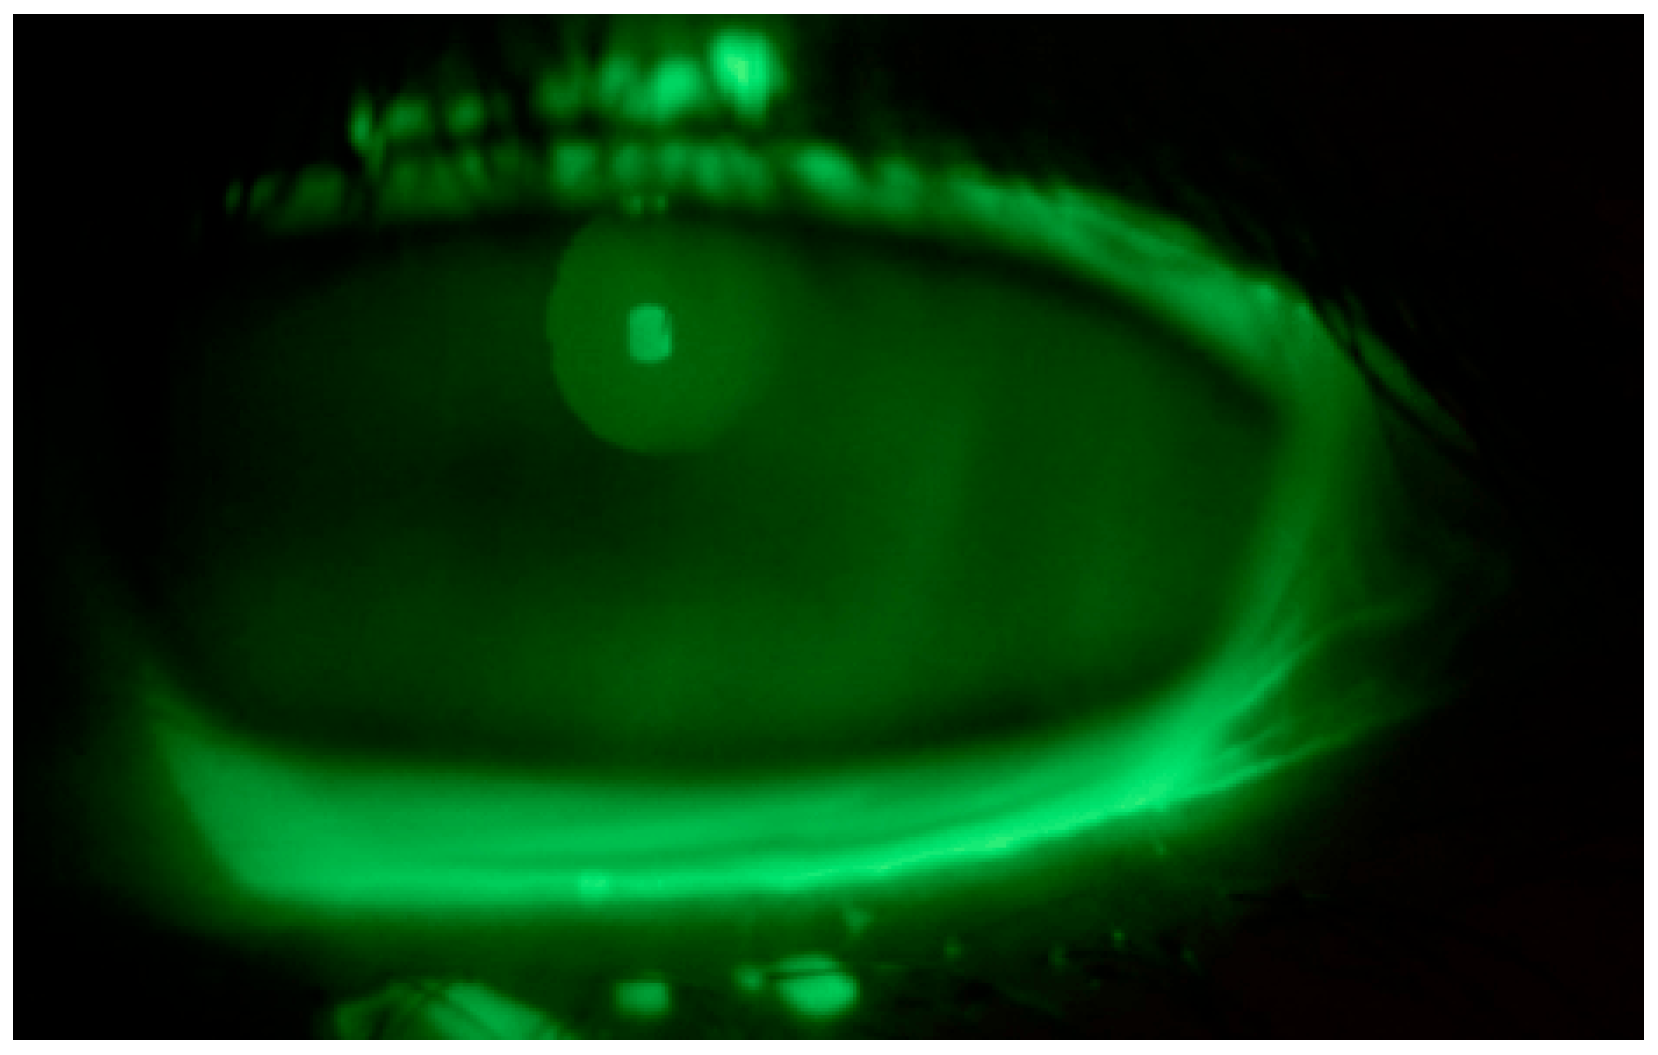

Tear substitute composed of hyaluronic acid, vitamin B2, vitamin E-TPGS, methylsulfonylmethane, and amino acids four times a day in both eyes and an antibiotic ointment (tetracycline + sulfamethylthiazole) before bedtime were prescribed; an ophthalmological follow up was performed after ten days: negative corneal Fluotest in both eyes (Figure 3 and Figure 4); TBUT right eye: 6 s, TBUT left eye: 5 s; Schirmer I test right eye: 10 mm, Schirmer I test left eye: 9 mm; and OSDI: 25.

Figure 4.

Fluotest on 10th day in the left eye.